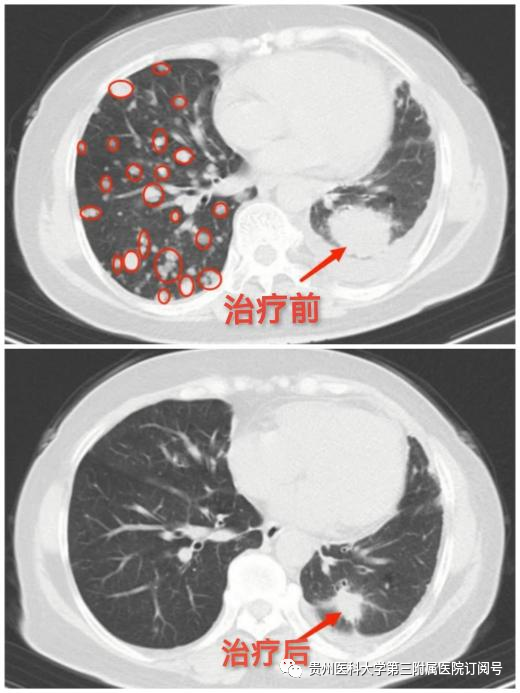

功夫不负有心人,经过肿瘤科的精心治疗和悉心护理,黄女士咳嗽、咳痰、胸痛、胸闷及呼吸困难已基本缓解,复查胸部CT提示多处病灶均较前明显缩小,精神状态明显好转。